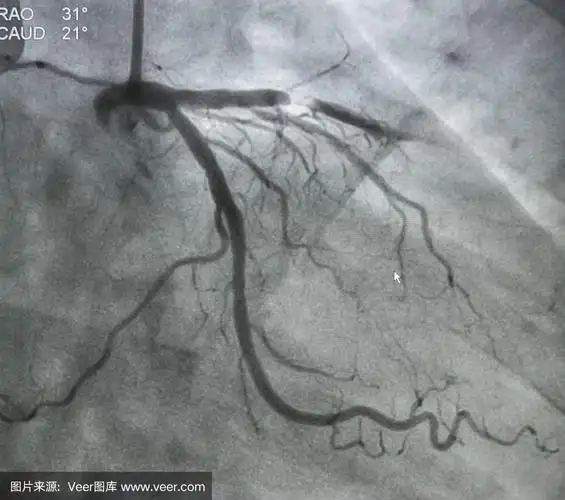

冠脉造影术——叶县二院介入科

冠状动脉狭窄的血管造影

冠状动脉造影,左冠状动脉造影

清晰的心脏冠脉造影图片!

第一例患者为中年女性,造影显示冠脉血流通畅,timi3级,继续药物治疗.

冠脉造影提示:左冠状动脉的前降支也有重度狭窄